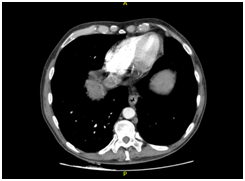

A CT angiography of the chest was performed, and a bilateral PE was found (Figure 1A). Anticoagulant therapy with low-molecular weight heparin was administered (1mg/kg, q12h). The CT angiography also revealed a liver mass and a CT of the abdomen was performed.

Figure 1 CT scanning. (A) Chest enhanced CT showing PE (arrow). (B) Enhanced CT of the abdominal region showing a large low-density lesion, sized 11.5x9.7 cm, in the right lobe (arrow). (C) Enhanced CT of the abdominal region showing tumour thrombus invasion of the IVC and RA (arrow). (D) Coronal reconstruction showing tumour thrombus invasion of the IVC and RA (arrow).

The CT revealed parenchymal heterogeneity of the liver, suggesting cirrhosis, and a sizeable lesion (11.5 x 9.7 cm) in the right lobe (Figure 1B). The lesion showed typical HCC image pattern, with an arterial phase enhancement and a venous/delayed phase washout. A hyperattenuating material in the portal vein (PV) lumen was also found, with no enhancement after contrast injection, inferring thrombotic/tumoral process; and a hyperattenuation in the IVC was also described (Figure 1C&D). Transthoracic echocardiogram confirmed tumoral invasion of the vena cava and right atrium.